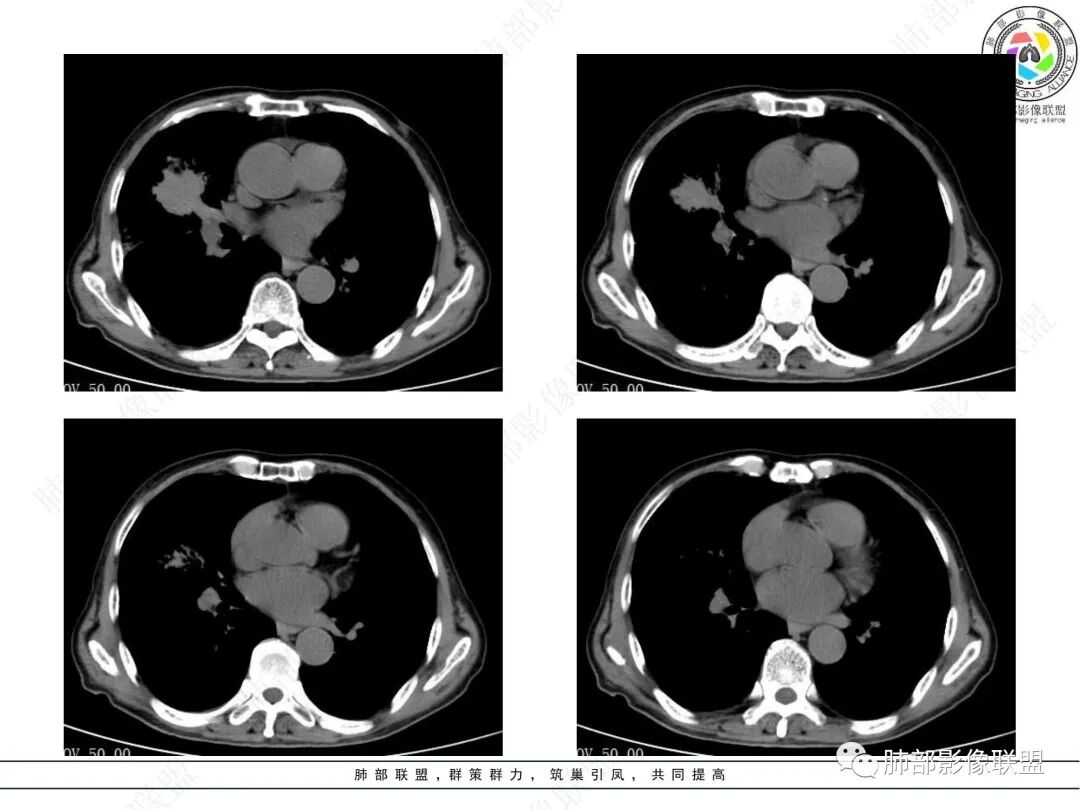

两个病灶独立,又有关联性,内侧病灶近端的支气管包绕在外侧病灶之中,但是走形自然

内部大片坏死区,其中还有不规则空洞

坏死腔内壁清,有强化环

血管征也明显

肺动脉在实变区走形自然,坏死腔周围受压推移,走形自然,坏死区内破坏

周围GGO,不能考虑癌性淋巴管炎

1、中央型肺癌:腔内为主——堵塞,不符合,支气管还是通畅的;腔外为主,不符合,会在肺门区周围团块,而不是远端

2、外朝内蔓延的恶性肿瘤:肺炎型肺癌——坏死腔内壁光滑,内部是坏死中空洞,而非假大空,放待排。癌肉瘤?不是一个类圆形团块。

3、炎性病变:觉得蛮符合的

支气管壁弥漫增厚,周围GGO,粘液腺癌啊GGO是靠近病灶区密度高,外围低,这一例不是很符合

这类坏死区内空洞,提示坏死液比较粘稠

不是液化坏死,液化坏死,这么大,有气体进来按理会形成液气平面

凝固性坏死

炎性多见,而且要警惕放线菌

炎性标志物升高,有悬浮气泡,是耍首先考虑放线菌